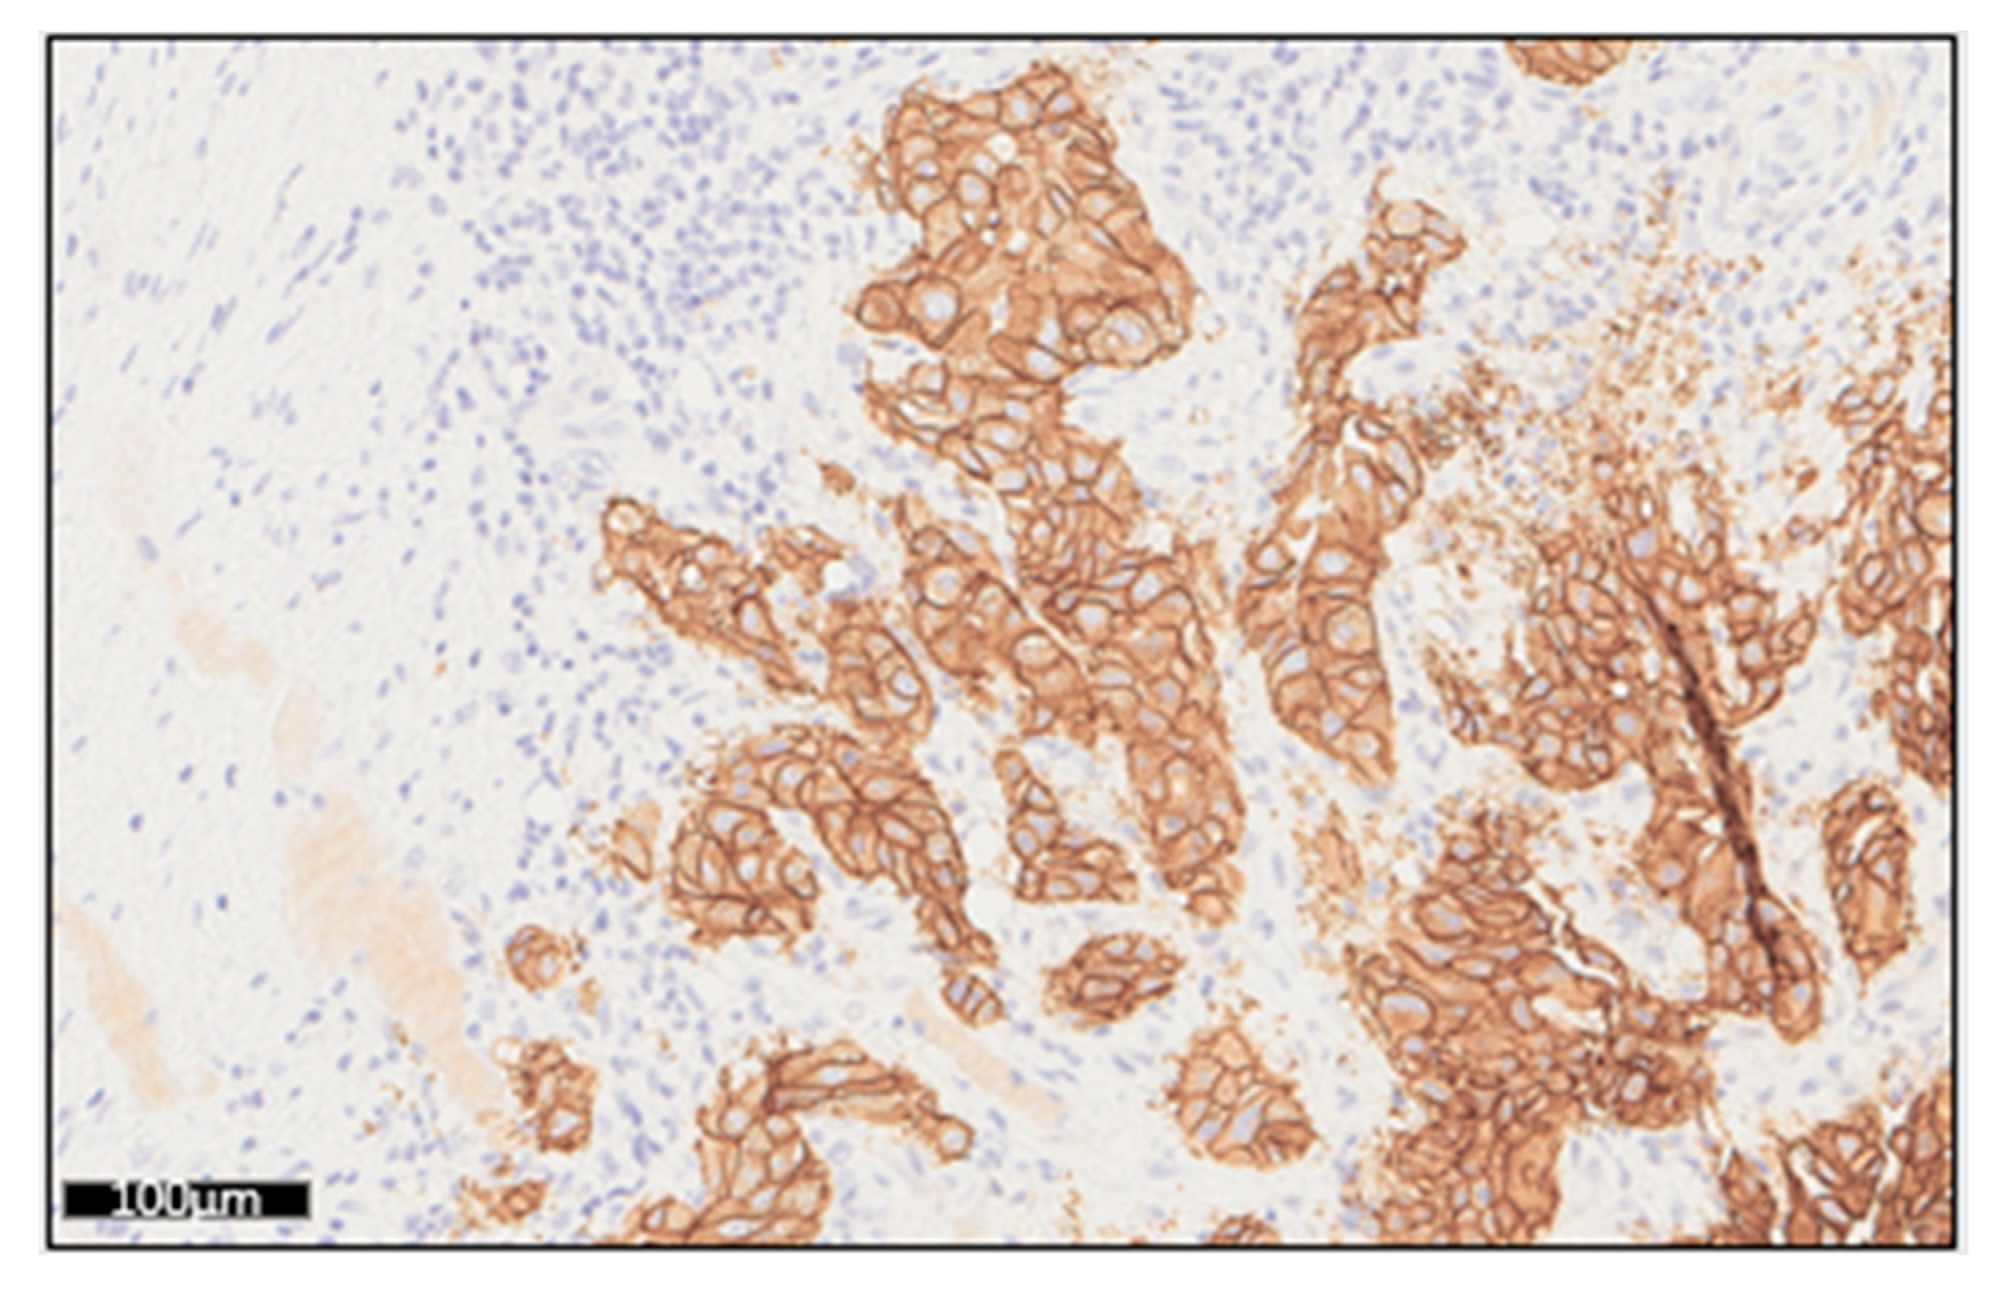

| Sample | MAPD | ERBB2 CNV | CNV Confidence Interval (5–95%) | Immunochemistry Staining Intensity |

|---|---|---|---|---|

| Patient 1 | 0.323 | 28.0 | 22.2–35.2 | Strong (+++) |

| Patient 2 | 0.360 | 9.5 | 7.5–12.0 | Strong (+++) |

| Patient 3 | 0.282 | 5.4 | 4.2–6.8 | Intermediate (++/+++) |

| Patient 4 | 0.334 | 12.0 | 8.3–16.5 | Low (+) |